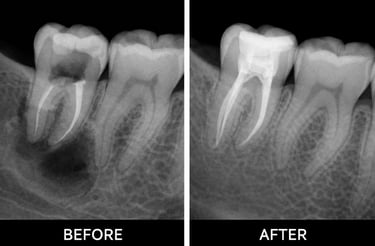

Root canal treatment removes infected or damaged pulp from inside a tooth. The pulp contains nerves and blood vessels, and infection can cause pain, swelling, or abscesses. During the procedure, the dentist cleans out the infection, shapes the root canals, and fills them with a safe material. Finally, the tooth is restored with a crown or filling to protect it. Root canals prevent infection from spreading and help keep your natural tooth

Examination & X-rays – determine the extent of infection or damage

Shaping & filling – shape canals and fill with biocompatible material

Temporary or permanent restoration – crown or filling placed to protect the tooth